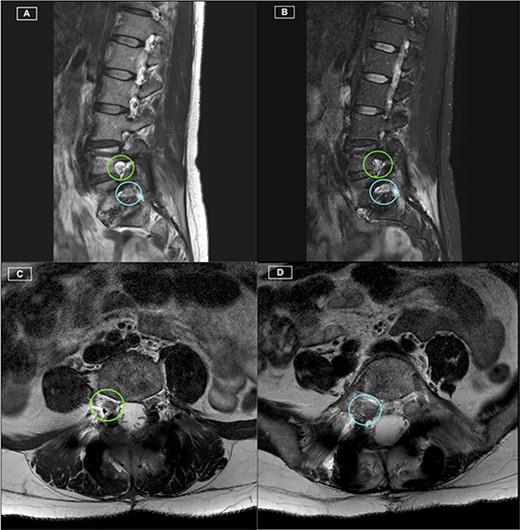

The patient recovered well, with resolution of her lower limb radiculopathy. Ongoing low back pain was managed by a multidisciplinary pain team. At 6 months post-operative, the patient experienced some recurrence of right leg pain. CT revealed excellent hardware position with no pseudarthrosis. MRI demonstrated adequate decompression of the descending and exiting L5 nerve roots, with minor perineural thickening within the right L5/S1 foramen. This patient was managed conservatively for her pain, given the lack of radiological pathology identified on CT and MRI. Figures 1–3 highlight the low artefact presence on both post-operative MRI and CT, allowing for optimal assessment of bony and neurological structures.

Postoperative MRI Lumbar spine. (A) Right-sided parasagittal slice of T2 Sequence MRI. Right L4/5 foramen (superior) and Right L5/S1 foramen (inferior) have been highlighted, with excellent definition of the Right L4 and L5 nerve roots. (B) Right-sided parasagittal slice of Short Tau Inversion Recovery (STIR) Sequence MRI. Exiting L5 nerve root is well visualised, with evident perineural thickening. (C) Axial slice of T2 Sequence MRI at the level of the L4/5 Foramen. The Right L4 nerve root is identified with excellent visualisation. (D) Axial slice of T2 Sequence MRI at the level of the L5/S1 Foramen. The Right L5 nerve root is identified with excellent visualisation.